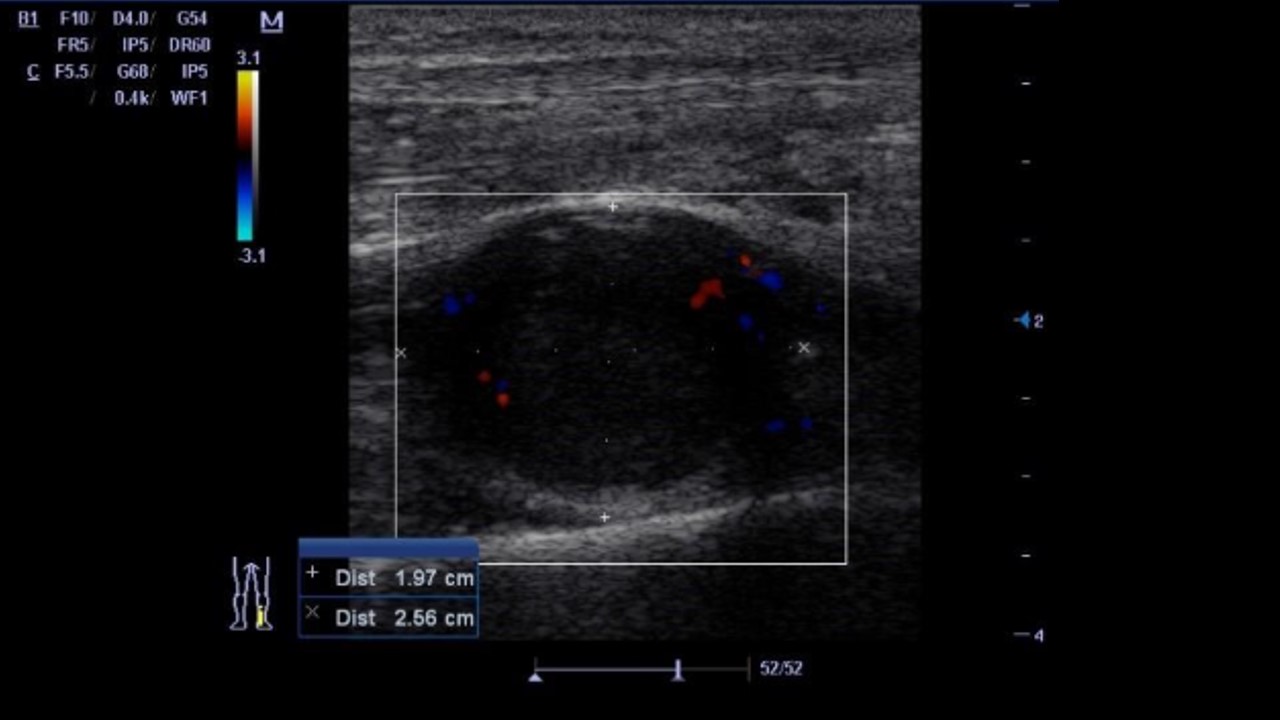

2018 Ecoscopia de atención primaria: imagen hipoecogénica de 2,5 x 2 cm redondeada por debajo de arteria tibial posterior con imagen Doppler periférica. Impresión diagnóstica: hematoma local. Plan: ecoscopia de control.

2018 Ecoscopia de control de atención primaria: persiste lesión, ovoide, bien delimitada, encapsulada de 2 x 2,5 cm, con vascularización interior, localizada en región muscular profunda a tercio medio del Tendón de Aquiles derecho. Plan: ecografía reglada.

2025 Ecografía reglada: nódulo sólido hipoecogénico, bien delimitado de 2,5 x 1,4 cm.